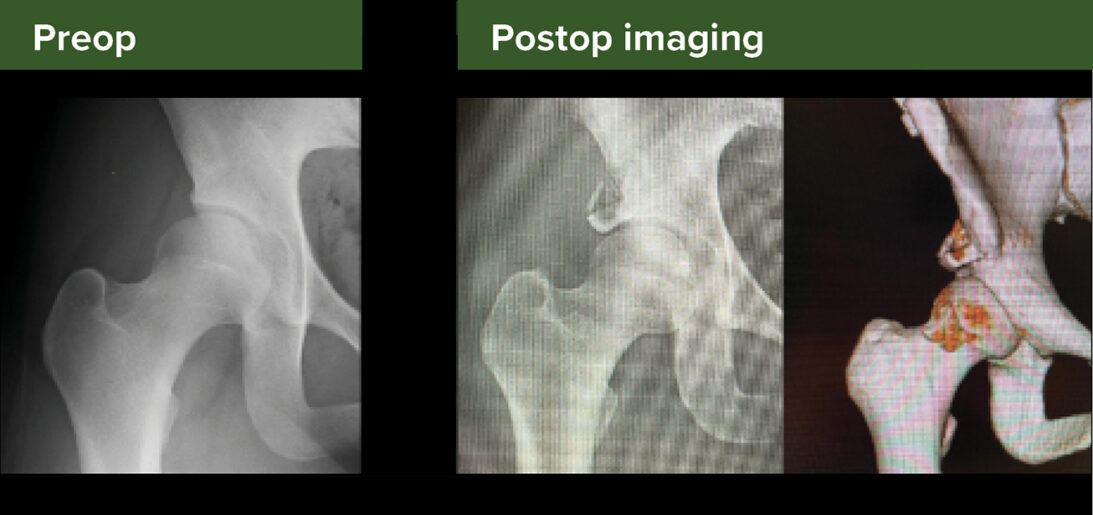

Figure 2: Preoperative versus postoperative radiographs demonstrating the outcomes of the endoscopic shelf acetabuloplasty procedure

The prepared graft is positioned in the slot using skewer wires and press-fit with cannulated bone tamps. Corticocancellous bone chips are packed above the shelf to ensure graft stability and promote osseous integration. Figure 2 demonstrates radiographic outcomes of this procedure.

This technique is suitable for patients with borderline or mild dysplasia, including a lateral center edge angle of 20 degrees to 25 degrees, Tönnis angle of 15 degrees or more, and a normal Shenton line. Contra-indications include severe dysplasia (lateral center edge angle <5 degrees), broken shenton line, significant femoral deformities, or osteoarthritis.></5>